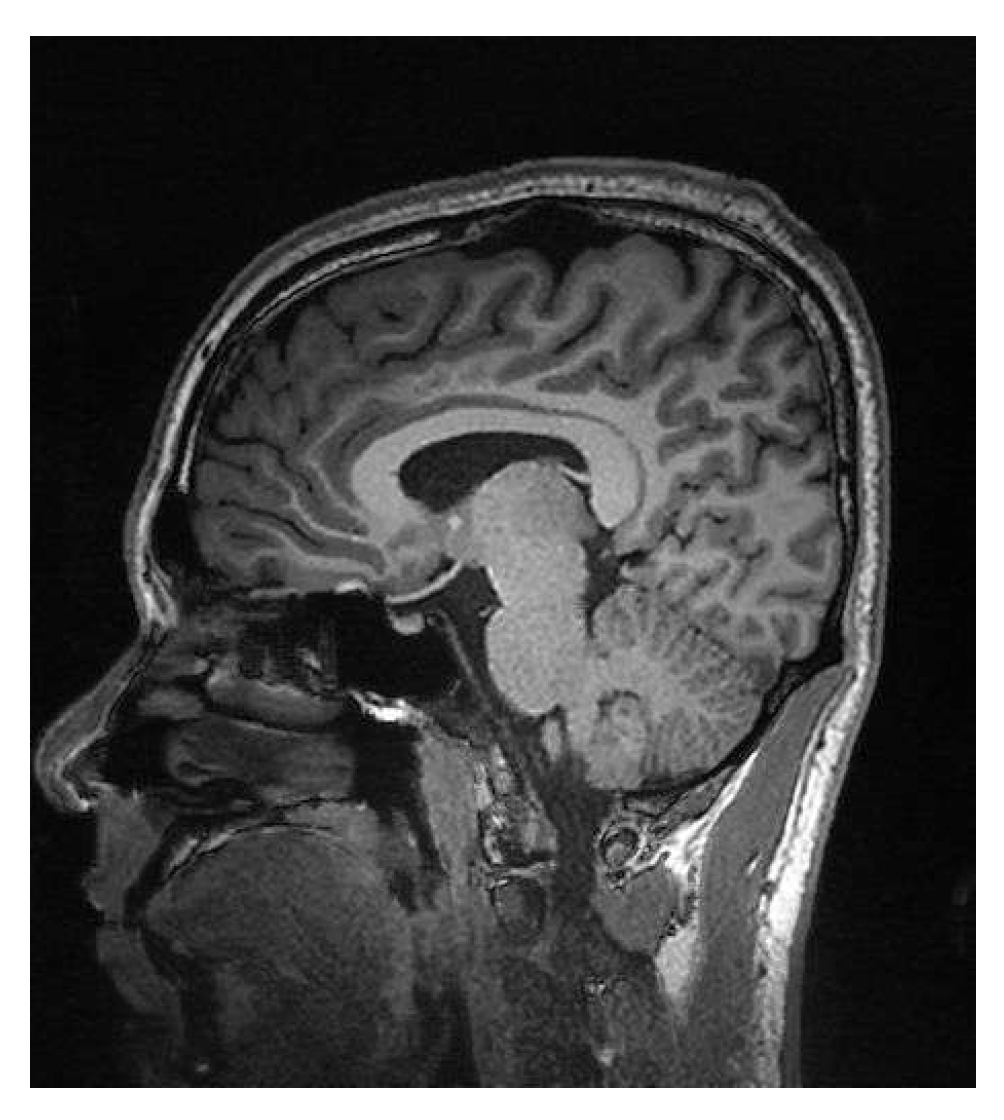

In Figure 7, the performance of Algorithm 4, which combines basis pursuit (BP) with DCT, is observed. This algorithm shows promising results for real applications. At a sampling rate of 35% (Figure 7a), the results show a PSNR of 22.79 dB and an SSIM of 0.55 (Table 2), reflecting a reasonable reconstruction quality. At sampling rates of 50% (Figure 7b) and 70% (Figure 7c), the PSNR improves significantly to 26.29 dB and 30.27 dB, with SSIMs of 0.77 and 0.91 (Table 3 and Table 4). The combination of basis pursuit with DCT and the use of a random measurement matrix faithful to the CS theory provides efficient compression (0.99) at higher sampling rates (70%) along with high-fidelity reconstruction. Although these results are expected due to the L1 norm applied to the reconstruction, it is worth noting that the image was resized to 128 × 128 for practical purposes. If a higher resolution were employed, the metrics would tend to rise.

Figure 7. Comparative images for Algorithm 4.